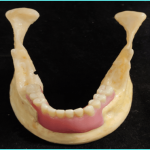

REMOVABLE IMPLANT SUPPORTED PROSTHESIS

DENTAL PROSTHETIC REHABILITATION OF A CLASS III DEFECT WITH ORAL IMPLANTS IN THE FIBULA AND SUPRACONSTRUCTION USING A BAR-SUPPORTED DENTURE

can also be proposed for patients wearing a removable denture, as well as O-ring retained dentures or telescopic retention17.